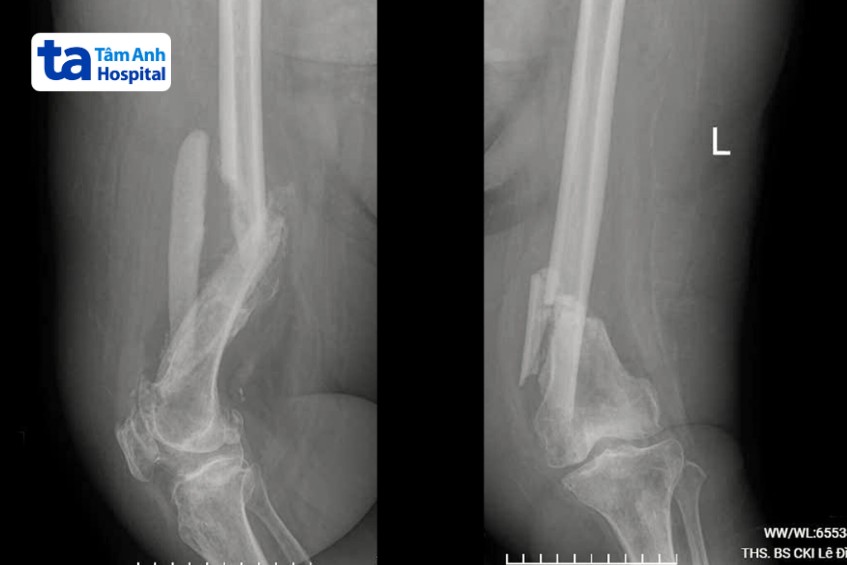

Kết quả chụp X-quang cho thấy người bệnh bị gãy xương đùi ở cả hai chân, mức độ gãy phức tạp. Bác sĩ nhận định bà Lành đang đối mặt các cơn đau đớn, đã xuất hiện tình trạng huyết khối ở động mạch phổi, đùi và cẳng chân hai bên. Cục huyết khối có thể gây tắc nghẽn mạch máu tại chỗ hoặc di chuyển theo dòng máu và gây tắc ở nơi khác, dẫn đến đột quỵ hoặc nhồi máu cơ tim.

Ngay sau khi chẩn đoán, các bác sĩ chỉ định phẫu thuật cho bà Lành bằng kỹ thuật nẹp vít kết hợp xương, thực hiện trước với chân trái. Theo kỹ thuật này, bác sĩ sẽ sắp xếp lại các mảnh xương gãy vào đúng vị trí, sau đó cố định bằng các nẹp vít kim loại được gắn vào bề ngoài của xương.

Bác sĩ Chọn cho biết đây là kỹ thuật không khó nhưng thách thức đặt ra là người bệnh đã nằm lâu một chỗ, nguy cơ huyết khối làm tắc nghẽn mạch máu trong lúc mổ. Đồng thời, do điều trị chậm trễ, các can xương (xương mềm mới tạo thành xung quanh chỗ gãy xương) đã mọc ra rất nhiều và hai đầu xương gãy chồng lên nhau làm ngắn chân.